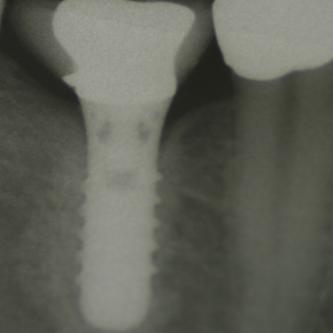

Exemple 7: Un implant au niveau de la deuxième prémolaire inférieure gauche.

Exemple 7: Le moignon vissé sur l'implant.